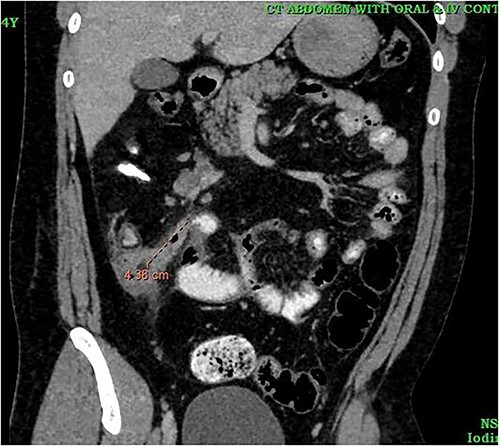

A 24-year-old male was admitted to the General Surgery out-patients clinic with a 2-week history of right iliac fossa pain. The patient had no other associated gastrointestinal symptoms. He had no other significant medical history but had undergone an open appendectomy for perforated appendicitis three months prior to the current presentation. Patient was vitally stable on presentation and the per abdominal examination showed tenderness at the McBurney’s point. A computed tomography (CT) scan of the abdomen revealed thickened and enhanced stump appendix along with adjacent fat stranding and multiple mesenteric nodes; suggestive of SA (Fig. 1). There was also a suggestion of adhesions and mild wall thickening of adjacent caecal wall with no evidence of collections or bowel mass (Fig. 2). Considering the upward trend seen in white blood cell count and the CT report, we planned the patient for a diagnostic laparoscopy. Pre-anaesthesia clearance was obtained.